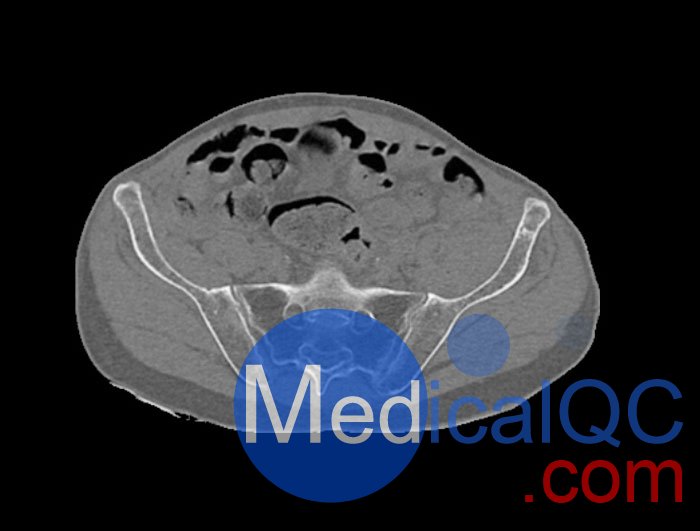

WEK54-01股骨頸骨折骨盆模型,WEK54-01骨盆模體模擬沒有靜脈造影劑的骨盆(天然)。它覆蓋了整個骨盆,直到第五腰椎。

左側(cè)股骨頸移位骨折。

該模型可用于 CT(包括 CBCT)和射線照相,以評估和優(yōu)化成像性能和后處理應(yīng)用,包括支持 AI 的應(yīng)用。它也適用于培訓(xùn)目的。

骨骼和軟組織的逼真模擬。